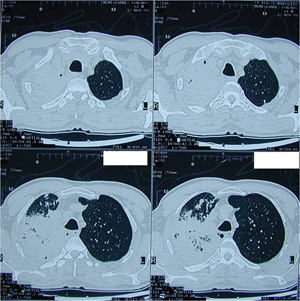

Εικόνα 2α-β

Αξονική τομογραφία θώρακος σε δύο επίπεδα. Πυκνο-ατελεκτατικά στοιχεία στον δεξιό άνω λοβό με ύπαρξη φλεγμονωδών στοιχείων.